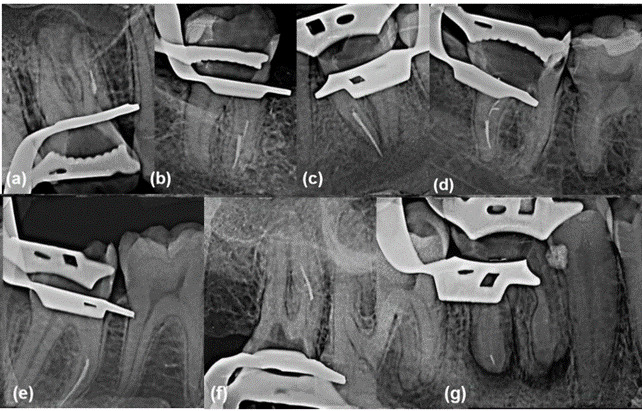

This study assessed the impact of pre-enlarging the root canal using a size 25 K-file on the fracture incidence of three reciprocating instruments after multiple uses. After a glide path performed with a size 15 K-file, the instruments (Reciproc R25, Reciproc Blue R25, and WaveOne Gold Primary) were initially used in 936 root canals. Then, for the second and third uses (933 and 927, respectively), a pre-enlargement using a size 25 K-file at the working length was done. Periapical radiographs assessed fragment location and length, and chi-square tests compared observed and expected frequencies (α = 5%). The fracture incidence during reuse ranged from 0% to 0.64%. Reciproc did not fracture during reuse (P = 0.99), but experienced two fractures in the third use (P = 0.000). Reciproc Blue and WaveOne Gold each had one fracture during the second (P = 0.000) and third (P = 0.000) uses. Following a pre-enlargement using a size 25 K-file for the second and third uses in 1,860 canals, only 6 instruments fractured (0.32%), suggesting that this approach may prolong the lifespan of these instruments and serve as an alternative for their reuse with a reduced risk of fracture.